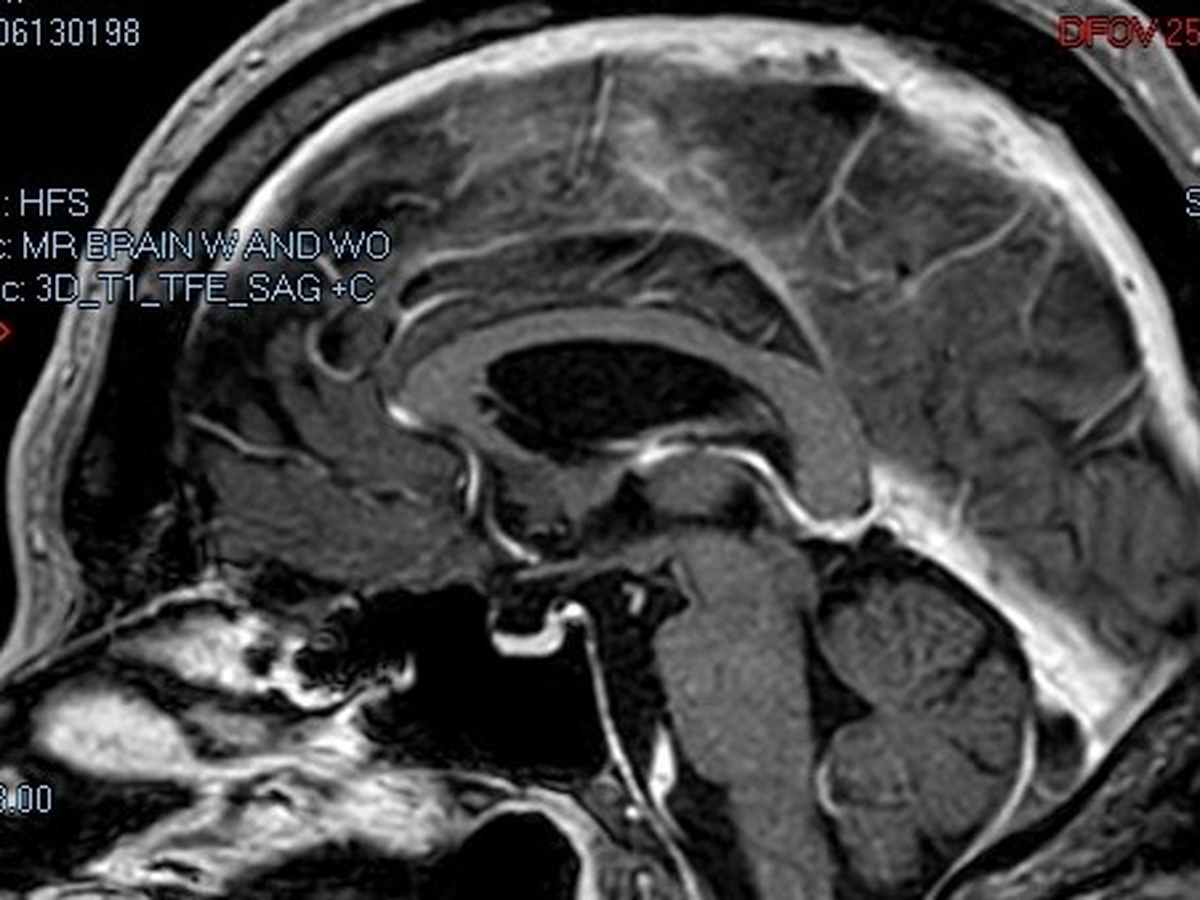

Hi. My name is Scott McDaniel. I was diagnosed with MS (multiple sclerosis) in July of 2025 after becoming ill in November of 2023. As of December 2025, my doctors are now leaning toward additional central nervous system, immune system and neurological diseases along with discovery in my MRIs of at least 2 strokes during my illness.

- My biggest fear right now is that the advanced hypertension and other medical issues are going to cause another stroke and I will not be able to communicate or move. The idea of being trapped in my own mind terrifies me beyond comprehension.